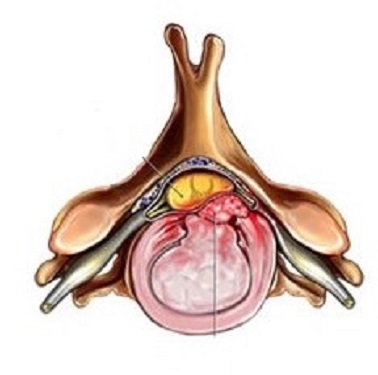

La HD cervicale consiste en l'expulsion d'un fragment de disque dans le canal médullaire. En cas de conflit avec les racines nerveuses ou la moelle épinière, des symptômes douloureux sont ressentis dans les épaules, bras ou mains. On parle alors de nevralgies cervico-brachiales.

L'arthrose cervicale consite en une "usure" des articulations. Des excroissances osseuses appelées "ostéophytes" peuvent apparaitre. S'ils sont trop développés, ils peuvent rétrécir le diamètre du canal et de foramens, comprimant des racines nerveuses ou la moelle epinière. Des symptômes douloureux sont ressenti dans les épaules, bras ou mains. On parle alors de névralgies cervico-brachiales.